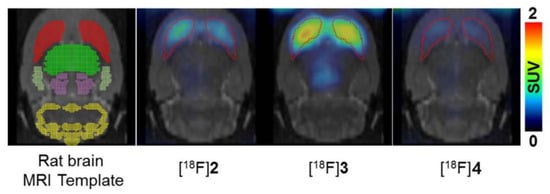

- Lee, B.C.; Moon, B.S.; Park, H.S.; Jung, J.H.; Park, D.D.; de Candia, M.; Denora, N.; Altomare, C.D.; Kim, S.E. The position of fluorine in CP-118,954 affects AChE inhibition potency and PET imaging quantification for AChE expression in the rat brain. Eur. J. Pharm. Sci. 2017, 109, 209–216. [Google Scholar] [CrossRef]